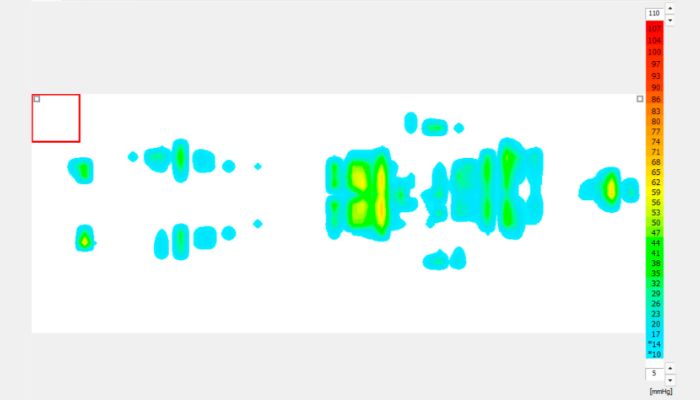

聞き取りの“つまずき”を見える化する

話し声と雑音が重なる場面の聞き取りを脳波で分析し、理解の流れを見える化。聴覚情報処理障害/聞き取り困難症(APD/LiD)の当事者に有効なトレーニング法、補助機器を提案します。